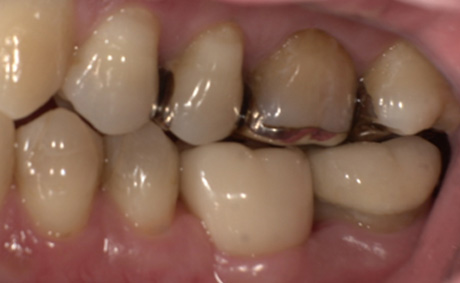

術前・術後の比較

| 術前 | 術後 |

|---|---|

![]() |

治療の経過を表示する